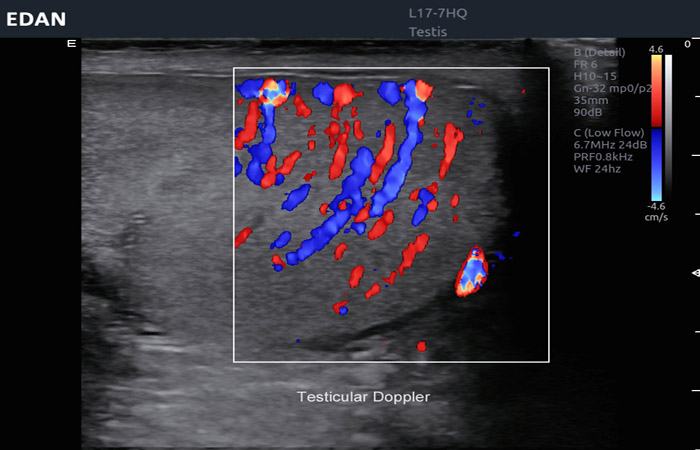

Επίσης καθίσταται δυνατή η απεικόνιση υγρικής συλλογής εντός του οσχέου (υδροκήλη, αιματοκήλη, πυοκήλη), ενώ με τη χρήση του έγχρωμου Doppler αποτελεί βασικό διαγνωστικό εργαλείο για τη διερεύνηση τυχόν κιρσοκήλης σε περιπτώσεις υπογονιμότητας.